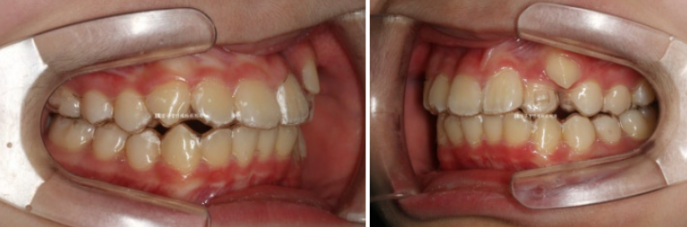

덧니 인비절라인 교정 장치 낀 첫날 모습입니다.

첫날은 필요한 어태치먼트 중 일부만 부착하여

아이가 장치에 적응할 수 있도록 도와줍니다.

처음부터 장치 끼기가 너무 어려우면 아이들의 의지가 꺾일 수 있습니다.